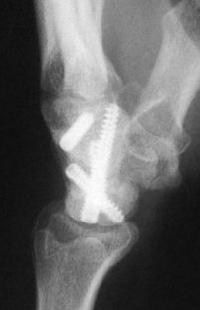

Intraoperatively, the distal pole cyst was eggshell thin with comminution into the ST joint. Stable fixation was not possible, even with a radial

styloid bone graft, and the distal pole was excised. Postoperatively, carpal instability was present.